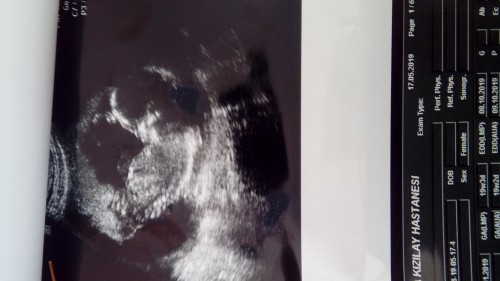

Merhaba canlarım çok şükür bu gün yavrunun cinsiyetini öğrendim ayrıntılı ultrasona girdim ve kesinleşti çok şükür kızım olacakmış çok sevindim gönlümden geçeni nasip etti Rabbim tatbiki farketmezdi ama dedim ilk evladım kız olsun inşallah benimle birlikte arkadaş gibi büyüsün çok şükür Rabbim dilimdeki duamı gönlümden geçeni düşürmüş içime hepimizin yavrularını sağ salim kucağımıza almamızı nasip etsin inşallah Rabbim ❤❤❤